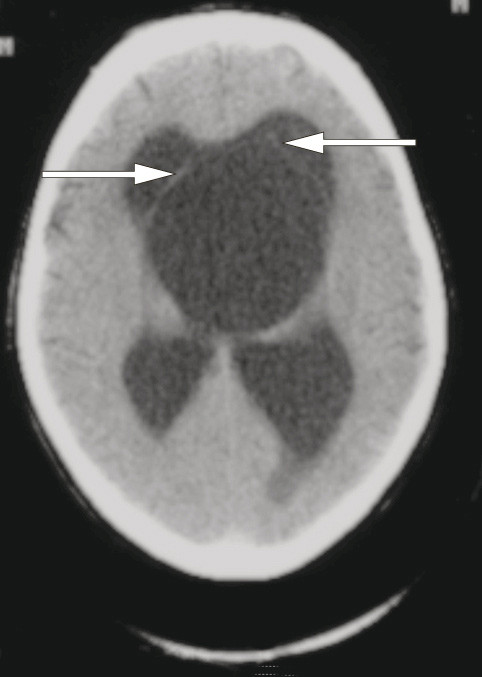

Ved innkomst ble det tatt et CT caput som viste obstruktiv hydrocephalus med dilatasjon av sideventrikler og komprimert tredje ventrikkel. Under innleggelsen ble pasienten tilsett av nevrolog, som mente at hydrocephalus kunne være årsaken til pasientens symptomer. Alternative forklaringer som høyt alkoholkonsum ble også diskutert.

Både datajournal og papirjournal ble grundig gjennomgått. Sykehistorien spenner over et langt tidsrom og illustreres med en tidslinje (fig 2). Allerede rundt 25 år før første innleggelse var han til vurdering for subjektive synsproblemer, og senere flere ganger for tåkesyn. Perimetri hadde påvist synsfeltdefekter, men pasienten hadde samarbeidsproblemer ved undersøkelsen og synsfeltdefektene varierte fra gang til gang, så man var usikker på om de var reelle. Ca. fem år senere ble han første gang vurdert av urolog, og i notatet blir det nevnt at han i flere år hadde hatt imperiøs vannlatingstrang og av og til inkontinens. Både da og senere var konklusjonen motorisk uhemmet blære. Som ledd i utredningen ble det omtrent 16 år før første innleggelse gjort en CT caput på samme lokalsykehus, og denne viste obstruktiv hydrocephalus (fig 3). Det var ikke beskrevet noen araknoidalcyste, men retrospektivt anes likevel araknoidalcysten på CT-bildene. Etter denne undersøkelsen ble han vurdert av nevrolog. Nevrologen fikk i sitt anamneseopptak kun frem «litt hyppig vannlating», og konkluderte med at pasienten hadde hatt hydrocephalus lenge og at cerebrospinalvæsketrykket ikke var vesentlig økt. Derfor henviste han ikke pasienten til nevrokirurg, men anbefalte kommunelegen å bestille en kontroll-CT om ca. 1/2 år. Noen annen oppfølging ble ikke anført. CT- funnet ble imidlertid ikke kontrollert, og diagnosen hydrocephalus nevnes ikke i pasientjournalen etter dette.